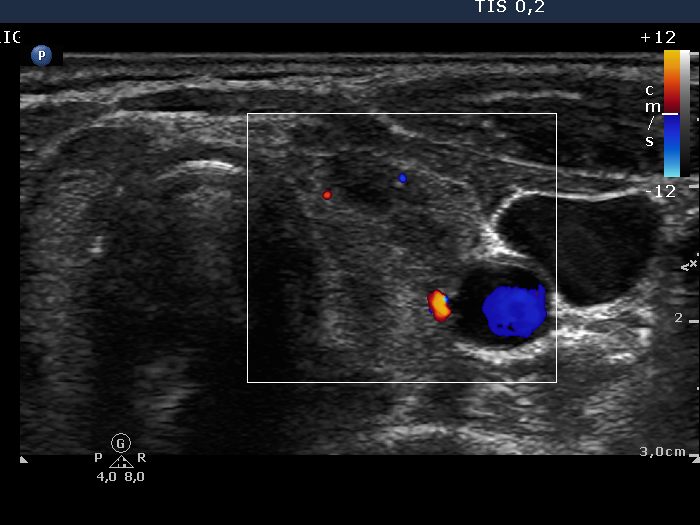

Chronic lymphocytic thyroiditis - Case 1. (ultrasonographic picture 8)

Left lobe, horizontal scan, color Doppler mode. The vascularization is decreased.